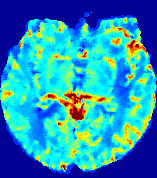

LesionRefer to captionRefer to captionRefer to captionRefer to captionRefer to captionRefer to caption𝐕rgbsubscript𝐕𝑟𝑔𝑏{\bf{V}}_{rgb}Refer to captionRefer to captionRefer to captionRefer to captionRefer to captionRefer to caption𝐕2subscriptnorm𝐕2{\|\bf{V}}\|_{2}Refer to captionRefer to captionRefer to captionRefer to captionRefer to captionRefer to captionRefer to caption3.53.53.52.82.82.82.12.12.11.41.41.40.70.70.70.00.00.0(mm/s)𝑚𝑚𝑠(mm/s)D𝐷DRefer to captionRefer to captionRefer to captionRefer to captionRefer to captionRefer to captionRefer to caption0.0200.0200.0200.0160.0160.0160.0120.0120.0120.0080.0080.0080.0040.0040.0040.0000.0000.000(mm2/s)𝑚superscript𝑚2𝑠(mm^{2}/s)Slice #1Slice #2Slice #3Slice #4Slice #5Slice #6

Figure 3: PIANO feature maps for one stroke patient, where the lesion is located in the left hemisphere. Top row: segmented stroke lesion region (white) on different slices, obtained from ISLES 2017. The corresponding slices for the PIANO feature maps are shown in the following rows.

For a better insight into an estimated velocity field 𝐕𝐕{\bf{V}} and diffusion field 𝐃𝐃{\bf{D}}, we compute the following maps: (1) 𝐕rgbsubscript𝐕𝑟𝑔𝑏{\bf{V}}_{rgb}: Color-coded orientation map of 𝐕=(Vx,Vy,Vz)T𝐕superscriptsuperscript𝑉𝑥superscript𝑉𝑦superscript𝑉𝑧𝑇{\bf{V}}=(V^{x},V^{y},V^{z})^{T}, obtained by normalizing 𝐕𝐕{\bf{V}} to unit length and mapping its 3 components to red, green, blue respectively; (2) 𝐕2subscriptnorm𝐕2\|{\bf{V}}\|_{2}: 222 norm of 𝐕𝐕{\bf{V}}; (3) D𝐷D: scalar field in Eq. 5.

Fig. 3 and Fig. 4 show the PIANO feature maps estimated from two ISLES 2017 patients: all are highly consistent with the lesion in both cases. Details of the blood flow trajectories are revealed in 𝐕rgbsubscript𝐕𝑟𝑔𝑏{\bf{V}}_{rgb} by the ridged patterns and the sharp changes of colors in the unaffected (right) hemisphere, while the flat patterns appearing within the lesion provide little directional information about the velocity and indicate low velocity magnitudes. Velocity magnitudes are more directly visualized via 𝐕2subscriptnorm𝐕2\|{\bf{V}}\|_{2}, from which one can easily locate the lesion where 𝐕2subscriptnorm𝐕2\|{\bf{V}}\|_{2} is low. D𝐷D also indicates lower diffusion values in the lesion, though with less contrast potentially due to the fact that it captures the accumulated effect of CA diffusion at the voxel-level.